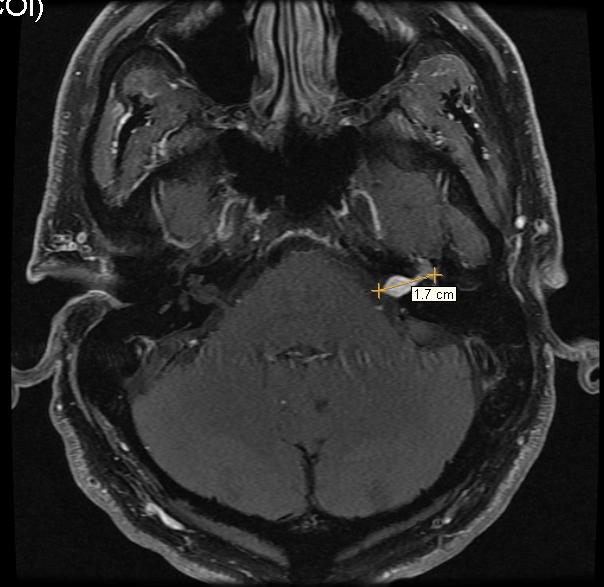

Here is the image from the MRI